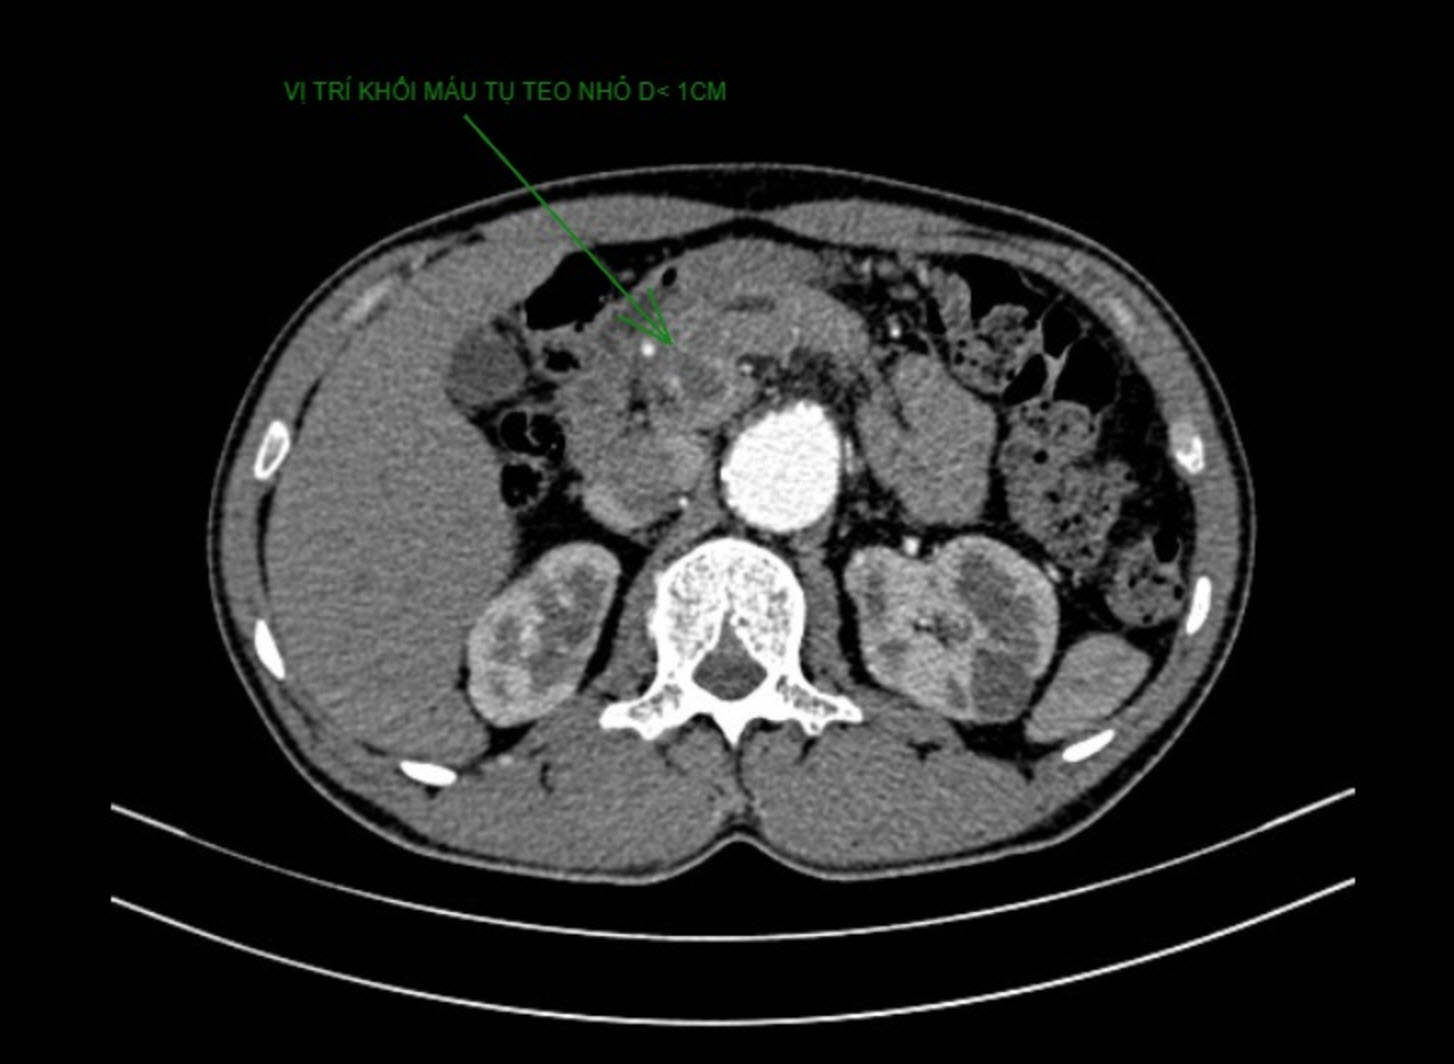

Hình CT cho thấy khối giả phình và khối máu tụ của người bệnh trước can thiệp

Sau khi thực hiện CT và nội soi dạ dày tá tràng, các bác sĩ cho biết anh V. bị xuất huyết tiêu hóa trên nghi do chảy máu đường mật từ khối máu tụ và giả phình kèm hiện tượng tắc mật do chèn ép. Khối máu tụ to với đường kính hơn 8cm (nằm vùng đầu và thân tụy) do giả phình động mạch (đường kính 28mm) đang hoạt động ngay phần chia đôi của động mạch thân tạng gây chèn ép gây tắc mật và nguy cơ vỡ lan rộng (do chảy máu tiếp diễn). Các xét nghiệm cho thấy rõ tình trạng người bệnh bị vàng da tắc mật như bilirubin tăng cao, men gan tăng gần 1000 UI/ml và thiếu máu.

Theo BS. Nguyễn Quang Thái Dương – Phó Trưởng Khoa Chẩn đoán hình ảnh, Trưởng Đơn vị can thiệp mạch tạng BV ĐHYD TPHCM, người bệnh bị phình động mạch chủ bụng và động mạch dưới đòn trên bệnh nền tăng huyết áp. Với tình trạng này, người bệnh có nguy cơ tử vong cao nếu túi giả phình tiếp tục phát triển, đồng thời có nguy cơ thúc đẩy biến chứng diễn tiến nặng như tắc mật, chảy máu tiêu hóa.